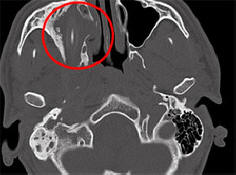

Neke su bolesti i povrede toliko neupadljive čovek može da živi s njima godinama unazad, a da ne sumnja u njih postojanje. Kao Amerikanac kome je trebalo gotovo dvije godine curenje sopstvene moždane tečnosti za curenje iz nosa, njemački državljanin uspio živjeti 15 godina s olovkom u glavi, izvještava Spiegel. Kako su rekli predstavnici univerzitetske bolnice Aachen, Sjeverna Rajna-Vestfalija, 24-godišnja Afganistanka porijeklo im je priteklo u pomoć još 2011. godine. Mladi osoba se žalila na uporne glavobolje, prehlade i pogoršanja vid na jedno oko. Dugo vremena lekari nisu mogli razumeti šta se događa. nisu radili računarsku tomografiju. Ispostavilo se to u mojoj glavi pacijent je sve to vrijeme bio olovka od 10 centimetara. On je koji se nalazi neposredno iznad desne očne utičnice mladića i postavljen na nju pritiska. Nijemac koji je želio ostati anoniman nije mogao objasniti odakle mu olovka dolazi u glavi, ali kasnije se seća kako je neuspešno padao u detinjstvu. Ljekari su joj skinuli strano tijelo sa glave mladići, i on se ubrzo oporavio. Tek krajem maja, nakon skoro godinu dana nakon operacije ljekari su odlučili posvetiti ovom slučaju zasebna konferencija, zahvaljujući kojoj su novinari saznali o tome. Ovo nije prvi put da osoba dugo uspijeva živite sa stranim predmetom u vašem tijelu. Dakle, 2007 starija Njemica koja boluje od glavobolje i krvarenja iz nosa, skinuli su olovku koja je tamo bila 50 godina.